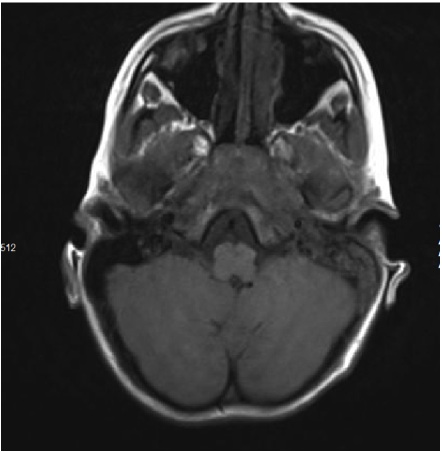

Si avviava terapia con ceftriaxone 100 mg/kg/die e desametasone 0,4 mg/kg/die ev e il giorno successivo veniva eseguita TC encefalo che escludeva la presenza di mastoidite confluente (Figura 3).

Figura 3. TC: completo opacamento mastoideo sinistro, orecchio medio sinistro e parte iniziale CUE.